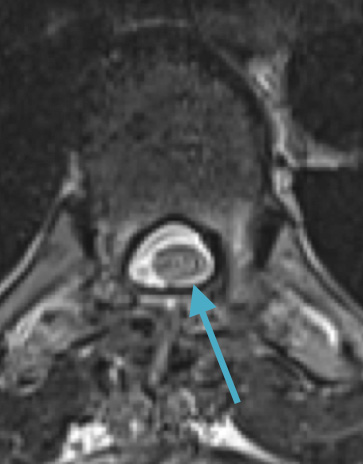

Postoperative MRI T1w demonstrating a gross total resection